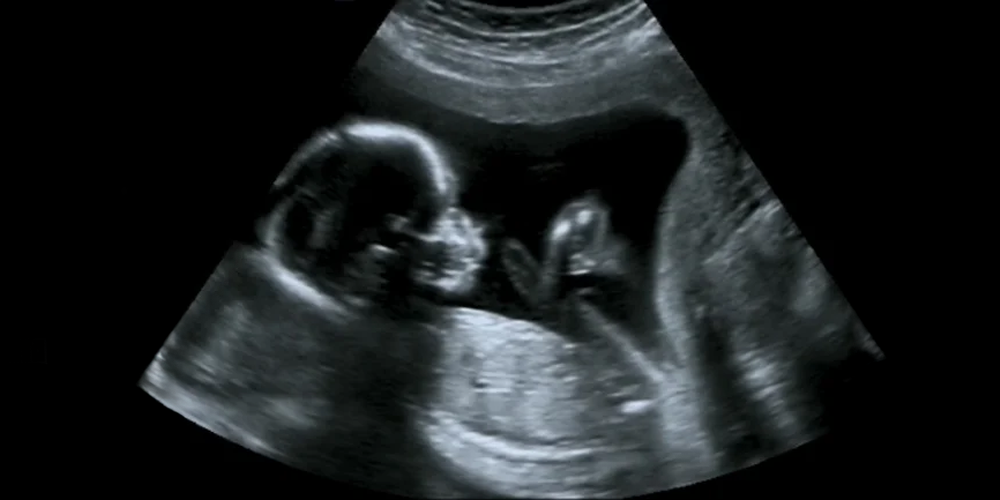

Bugün ultrason bize incelediği dokuların sıvı veya katı olmalarını bilgisayar yardımıyla işleyerek bir resim oluşturuyor. Daha doğrusu anlık resimler oluşturuyor. Ve biz bu kesitleri kafamızda birleştirerek anne karnındaki bebeği muayene edebiliyoruz.

Ancak, bu görüntüleme bir ışık yardımıyla çekilen bir fotoğraf olmadığı için kuralları ve yorumu farklı. Bu nedenle, tıp dışındaki bakış açısından bebeğin karaciğerinin bile(!) görülebilmesi mümkün iken, ellerinin görülememesi çok daha kolay bir işmiş gibi algılanabiliyor. Oysa gerçekte durum çok farklı. Ultrason katıları ve sıvıları birbirinden kolay ayırdığı için, bebeğin idrar torbası, midesi, kalbi çok rahat görülebilirken, ayaklarının eğik olması duruma göre gözden kaçabilir.